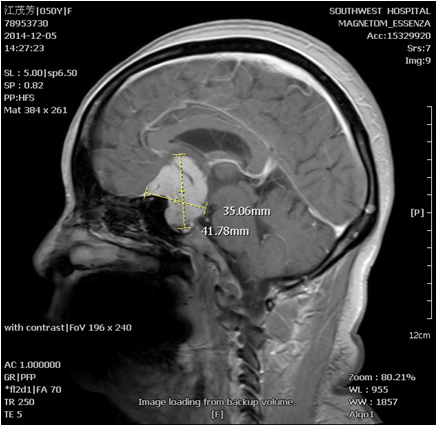

“經(jīng)檢查,秦某被確診為鞍結(jié)節(jié)腦膜瘤,她左眼失明和長期頭痛的根源在大腦內(nèi),而不是在眼部。”手術(shù)主刀醫(yī)生、該院神經(jīng)外科副主任吳南教授說,由于大部分腦膜瘤長在中線部位,腦腫瘤逐漸長大后很容易壓迫視神經(jīng),造成患者視力下降甚至失明。但除偶發(fā)頭部疼痛外,并無其他明顯癥狀,所以腦部腫瘤引起的視力下降或失明容易被誤診為眼部疾病。

吳南表示:“由于秦某幾乎失明已近3個(gè)月,左眼視神經(jīng)已經(jīng)被腫瘤壓迫的非?!嗳酢?。如果仍然用常規(guī)開顱或鎖孔手術(shù)切除大腦內(nèi)腫瘤,肯定會在手術(shù)中觸碰正常腦組織和視神經(jīng),有可能很輕微的觸碰,就造成神經(jīng)系統(tǒng)不可逆的破壞。”

手術(shù)前